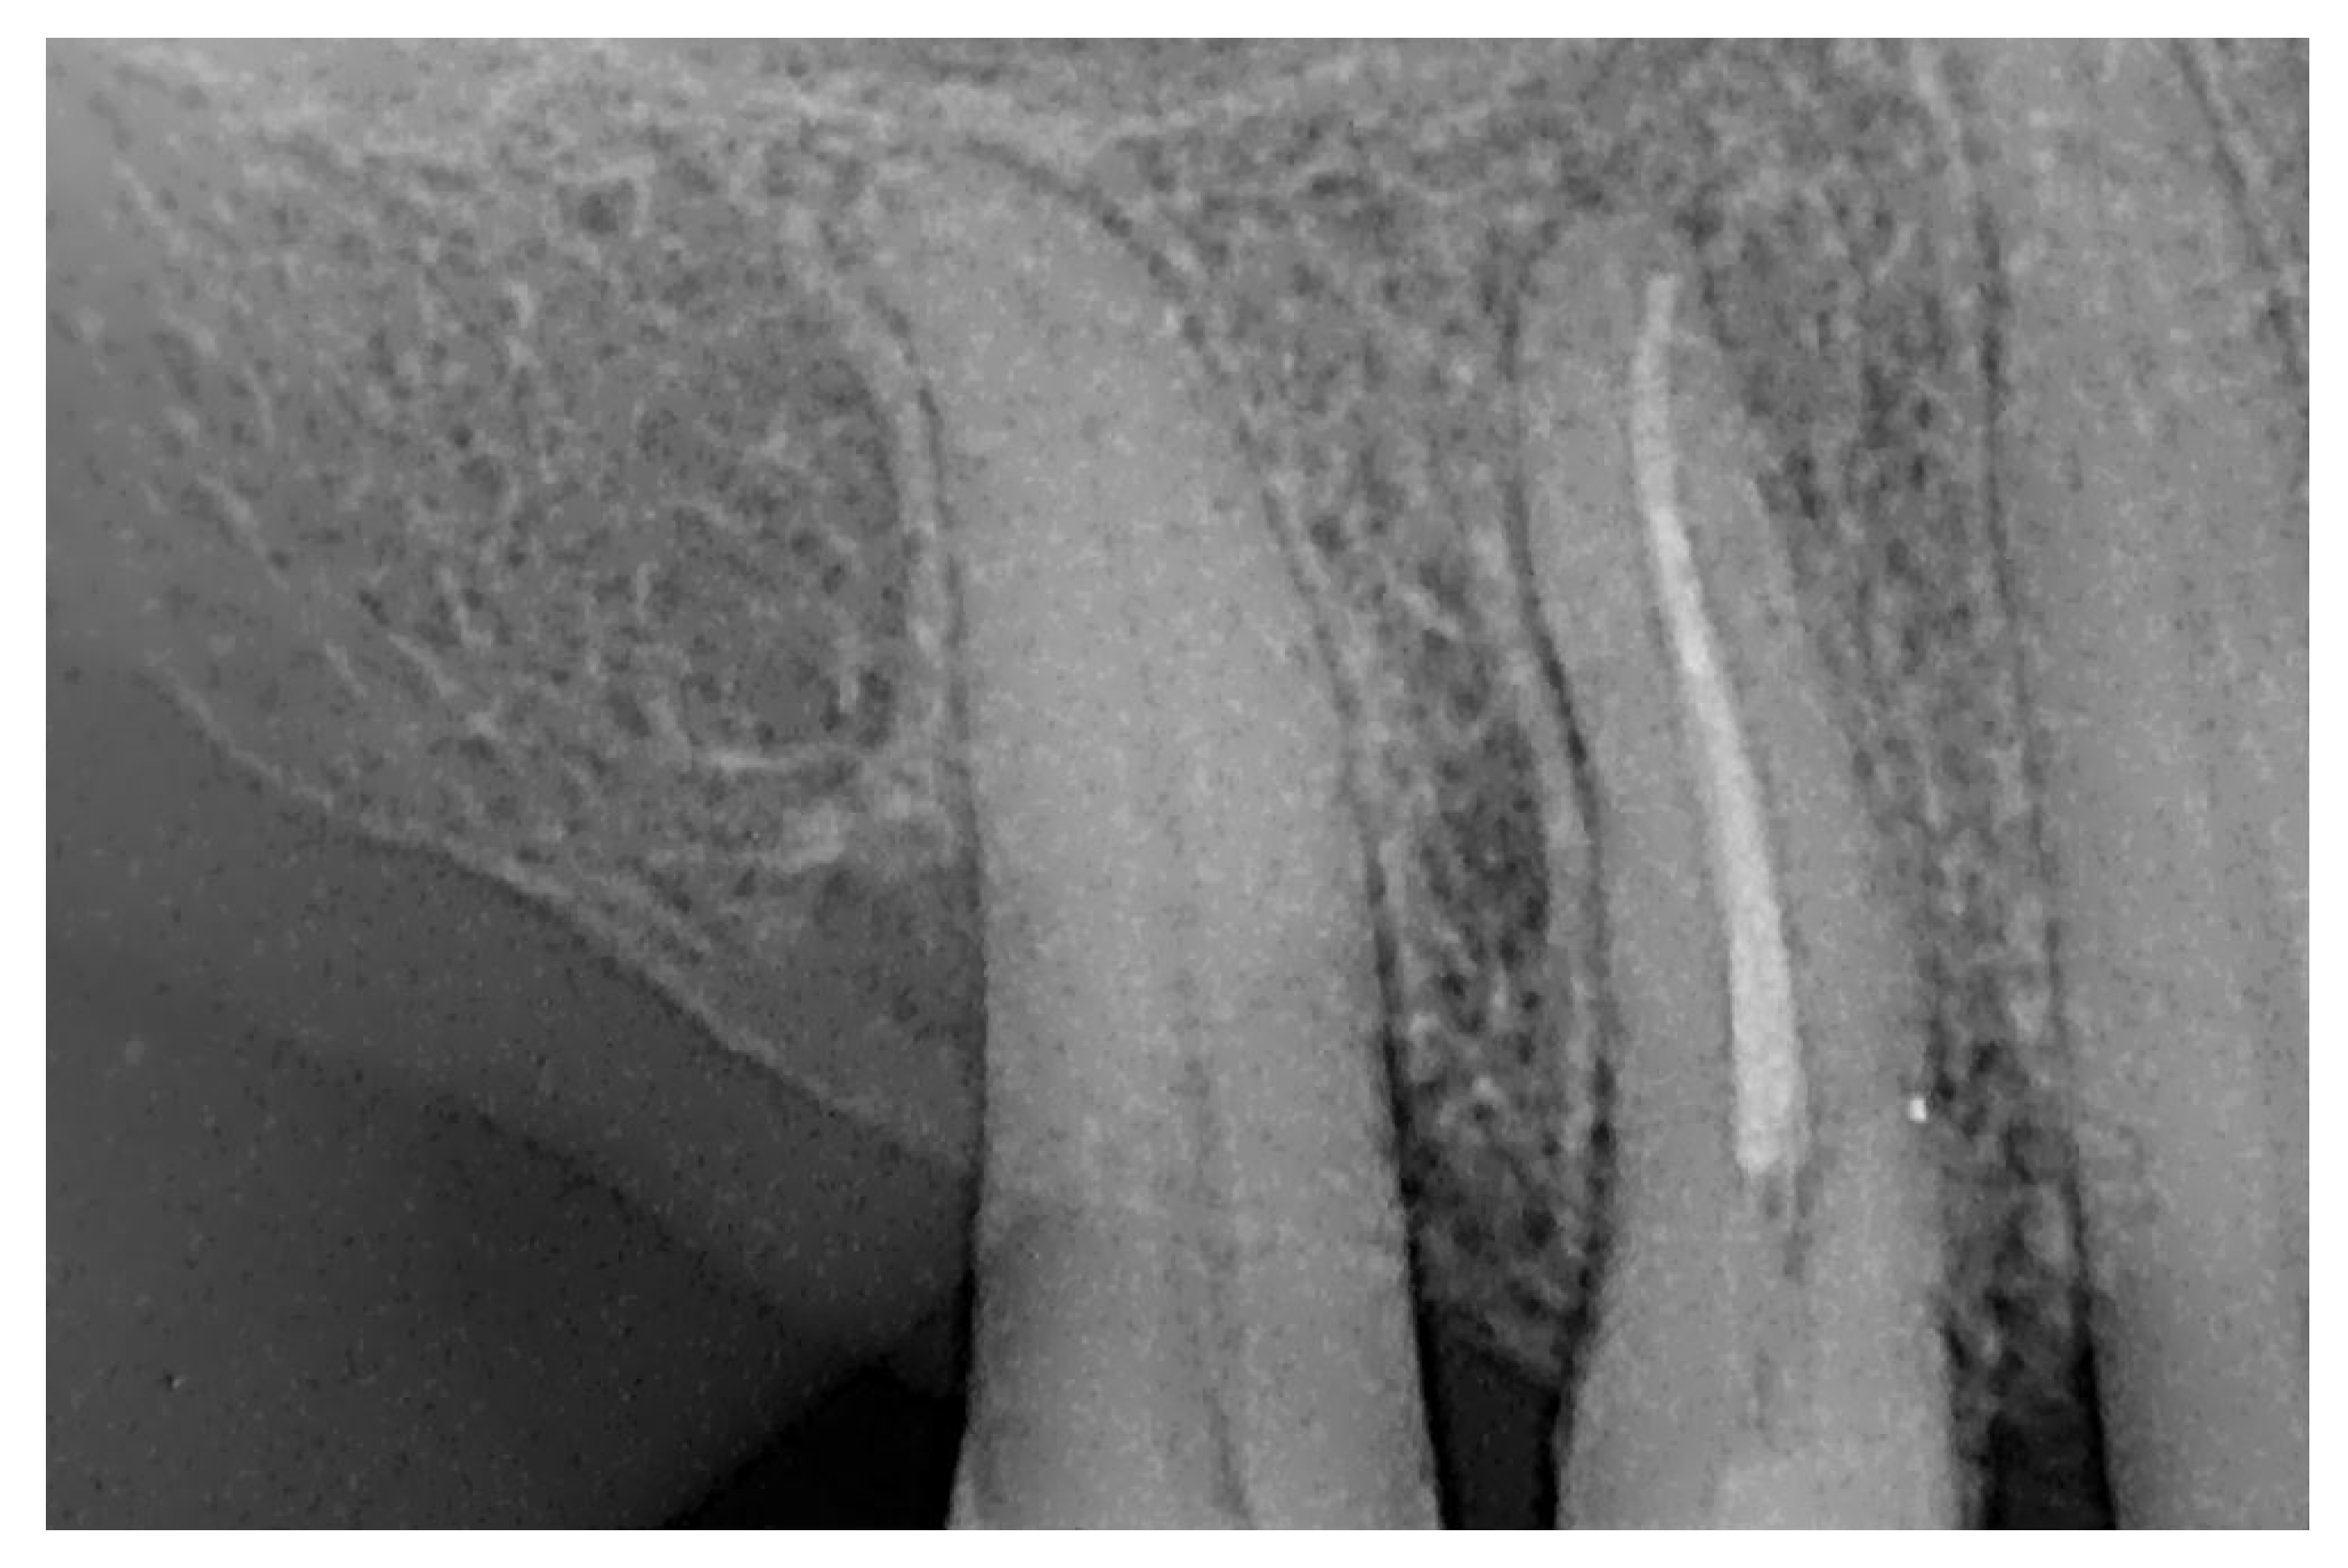

Signs of parafunctional habits and bruxism were noted, along with compromised periodontal status and poor oral hygiene. Multiple carious lesions were present, and the patient exhibited a gag reflex during examination. The patient presented complaining of spontaneous pain and pain upon mastication in the right maxillary region. Tooth 1.4 showed significant pain on percussion and a pathological periodontal probing depth at the mesiolingual site. Intraoral radiography revealed an extensive cervical root resorption zone and a periapical lesion (PL) (Figure 1).

Figure 1.

Intraoral radiography of tooth 1.4 showing root resorption, LP and EPL with mesiocervical widening of the lamina dura space.